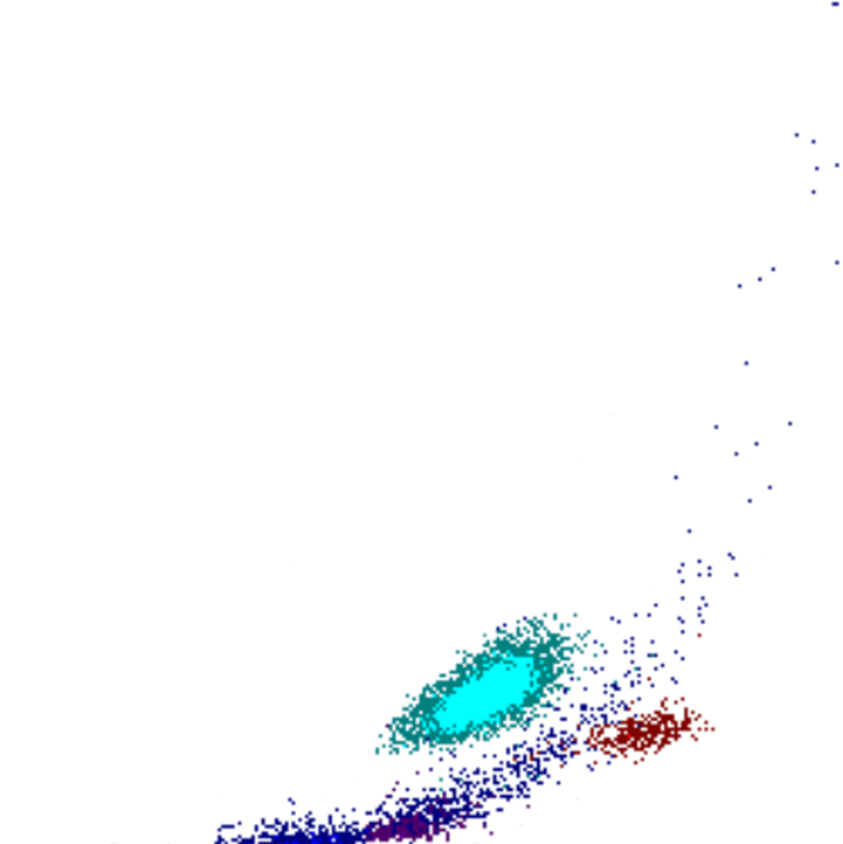

Side Fluorescence

Le signal SFL reflète la teneur en acides nucléiques des cellules. Les cellules avec un SFL élevé contiennent davantage d’ARN et/ou d’ADN, ce qui indique souvent une activité ou une prolifération accrue. Il existe une corrélation limitée entre le SFL et le FSC ; bien que les cellules plus grandes présentent généralement un SFL plus élevé, des exceptions existent, telles que des blastes avec un SFL relativement faible ou des lymphocytes activés avec un SFL élevé malgré leur plus petite taille.

SFL scatter

SFL faible

SFL élevé